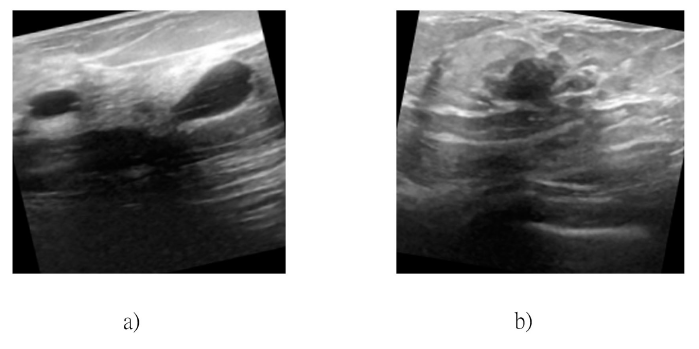

Para este trabajo se seleccionó un dataset público que se encuentra disponible en el sitio Kaggle (Adithya, 2020), las imágenes están organizadas en dos clases: benigno y maligno como se muestra en la Figura 1. El dataset contiene 9016 imágenes en total con un tamaño promedio de 500 x 500 pixeles en un formato png, entre estas se encuentran múltiples imágenes de mastografías presentes en el dataset, la Tabla 1 muestra en conjunto de datos.

Figura 1 Imágenes del dataset: a) Benigno y b) maligno.